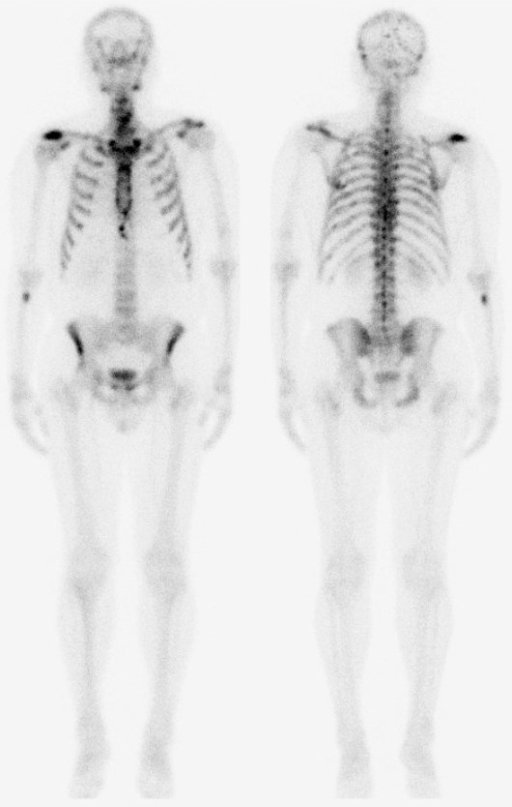

Jednofotonová emisní výpočetní tomografie (SPECT)

SPECT je zobrazovací metoda, která dokáže zobrazit prostorové rozložení radiofarmaka v lidském těle. Gantry umožňuje pohyb detektoru kolem těla pacienta v malých úhlových krocích, případně jsou přístroje vybavovány zařízením, které automaticky udržuje optimální vzdálenost detektoru od povrchu těla pacienta. Při vyšetření se otáčením jednoho až tří detektorů kolem těla pacienta zhotovuje velké množství projekcí. Získaná data jsou uchována v paměti počítače pro další zpracování a rekonstrukci obrazů ve třech základních vzájemně kolmých rovinách - transversální, frontální a sagitální. Na rozdíl od rentgenových metod, které zobrazují tělní struktury, se tato metoda soustředí na zobrazení funkce daných orgánů.

SPECT

SPECT.